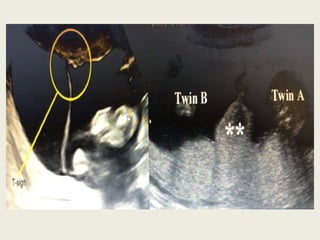

3. Multiple pregnancy:

• Chorionicity

– Type of placentation

– Prenatally by USG

– Postnatally by examining membranes

• Usg determination for chorionicity

– Numbers of sacs

– Placenta

– Sex

– Intertwin membrane

– Lambda & T sign

Ideal time to assessing chorionicity is before 14 weeks

Heterotopic pregnancy